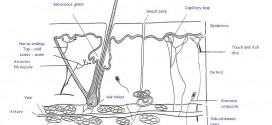

La pápula. Elevación eruptiva epitelial de pequeño tamaño sólida circunscrita de la piel y más o menos redondeada que se eleva sobre el nivel de la piel y cuya consistencia es dura. Está provocada por un aumento de las células de la epidermis, de la dermis o de ambas que ordinariamente termina por descamación y aparece en muchas afecciones dermatológicas …

La paquidermia. Hipertrofia es el espesamiento anormal o patológico de la piel, por causas diversas, como edemas o inflamaciones crónicas, etc. La hipertrofia de la piel y tejido subcutáneo, puede alcanzar a veces proporciones anormales grandes del espesor de la piel. Pues bien una vez diagnosticado cual es la enfermedad o nombre de dicha patología, lo primero que debería de …

El pénfigo. Es la enfermedad ampollosa más grave. Es una de las pocas enfermedades de la piel que conlleva peligro para la vida del paciente. Su origen es autoinmune y afecta la piel y las mucosas. El fenómeno etiopatogénica causante de esta enfermedad es la perdida de la cohesión entre células epidérmicas y como consecuencia, se origina la formación de …

El papiloma. Hipertrofia de las papilas de una superficie cutánea o mucosa. Tumor epitelial benigno que se presenta como una excrecencia de superficie irregular y diversos tamaños. Neoplasia epitelial benigna que presenta una disposición ramificada o lobulillar. Se produce en la piel especialmente de manos y pies y por lesiones en las membranas mucosas de la boca y de las …